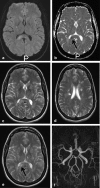

Background and purpose: The splenium of the corpus callosum is the most posterior part of the corpus callosum. Its embryological development, anatomy, vascularization, function, imaging of pathology, possible pathophysiological mechanisms by which pathology may develop and the clinical consequences are discussed.

Methods: A literature-based description is provided on development, anatomy and function. MR and CT images are used to demonstrate pathology. The majority of pathology, known to affect the splenium, and the clinical effects are described in three subsections: (A) limited to the splenium, with elaboration on pathophysiology of reversible splenial lesions, (B) pathology in the cerebral white matter extending into or deriving from the splenium, with special emphasis on tumors, and (C) splenial involvement in generalized conditions affecting the entire brain, with a hypothesis for pathophysiological mechanisms for the different diseases.

Results: The development of the splenium is preceded by the formation of the hippocampal commissure. It is bordered by the falx and the tentorium and is perfused by the anterior and posterior circulation. It contains different caliber axonal fibers and the most compact area of callosal glial cells. These findings may explain the affinity of specific forms of pathology for this region. The fibers interconnect the temporal and occipital regions of both hemispheres reciprocally and are important in language, visuospatial information transfer and behavior. Acquired pathology may lead to changes in consciousness.